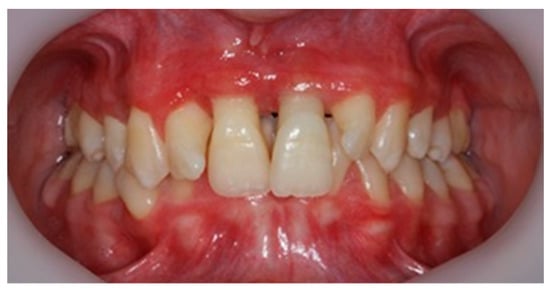

The plaque index score registered and bleeding upon probing (BOP) were 100%. The initial probing depth (PD) was 10 mm at the left central incisors (mesial) and 8–9 mm at the other proximal sites of the both upper central incisors. The tooth mobility (Miller Classification) was Class 2 for both the maxillary central and lateral incisors (Figure 2).

The periodontal diagnostic was stage III, grade C periodontitis. Stage III of periodontitis, in this case, was defined based on the severity (interdental CAL ≥ 5mm, radiographic bone loses extending to the apical third of the root) and complexity of management (probing depth > 6 mm, vertical and horizontal bone loss, tooth mobility degree ≥ 2, and masticatory dysfunction). The grade of periodontitis was estimated with direct or indirect evidence of % bone loss/age > 1.0 and destruction exceeding biofilm deposits (suggestive of rapid progression and early onset disease) [12,13,14]. The orthodontic diagnostic was class II, division 1 malocclusion (Angle classification) and deep bite malocclusion, with dental malposition primary and secondary to the periodontal disease. The smile line was altered due to the overgrowth of gingival tissue at the maxillary tooth. Additionally, following vitality and percussion tests, both the maxillary and mandibular incisors were vital and without any signs of pulpal involvement.

After 3 months of phase 1 of periodontal treatment, the patient returned to the clinic for supportive periodontal therapy (Figure 5). The clinically measured gingiva recession was about 6 mm for the maxillary central incisors and 4 mm for the lateral incisors. According to the Miller classification—class III gingival recession—vestibular marginal tissue recession extends to the mucogingival junction. Loss of interdental bone is apical to the CEJ but coronal to the apical extent of the vestibular marginal tissue recession (Figure 5).

The mobility of the teeth (Miller classification) was maintained at Class 2 for the two maxillary central incisors. This mobility was a result of inflammatory edema but also of the high degree of alveolar bone loss (Figure 6). The patient had no discomfort or pain.